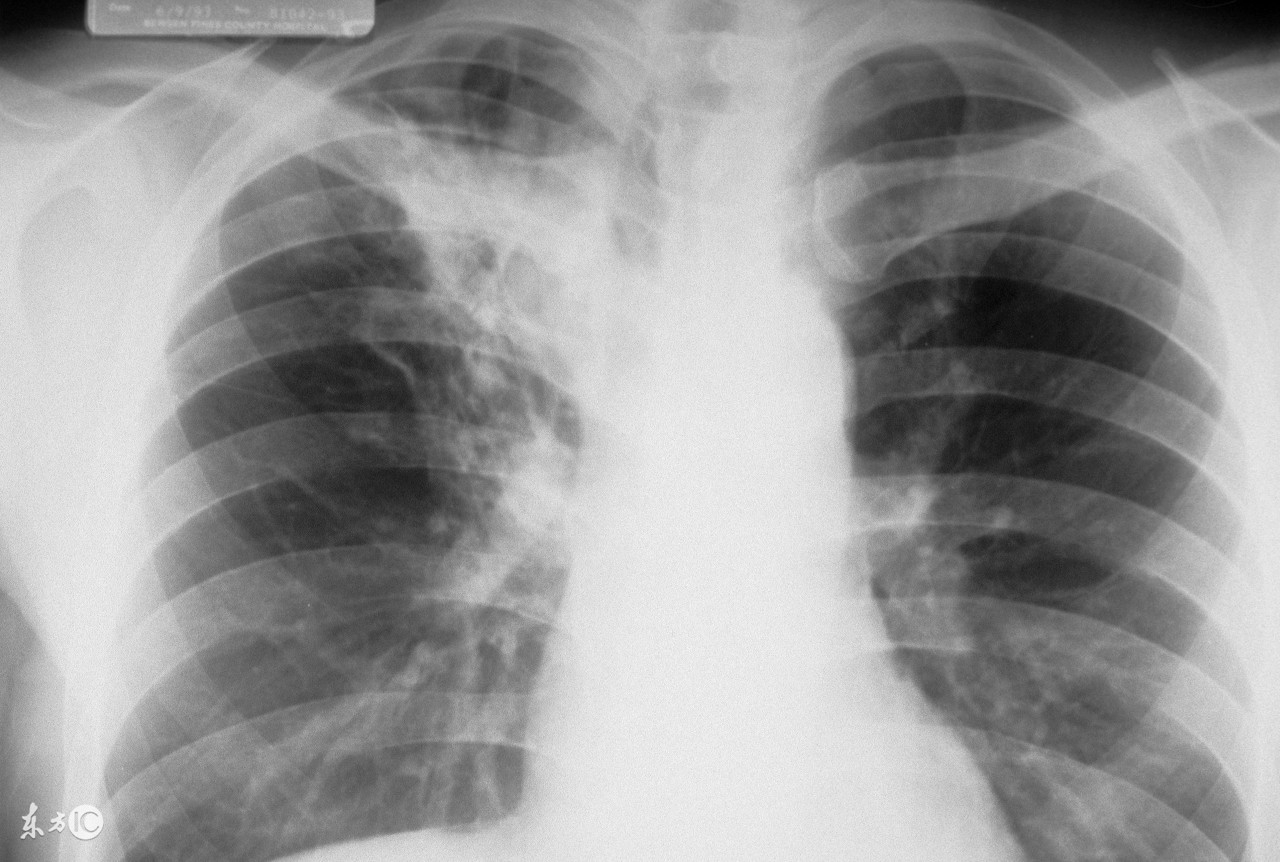

肺结核在现在的生活中已经是很常见的疾病了,对于肺结核的治疗,患者一般离不开药物治疗。药物主要是控制肺结核的病情,降低患者的死亡率。但是用药物治愈肺结核疾病是困难的。下面我们一起来了解怎样可以治愈肺结核。

临床上对于肺结核的治疗有初、复治之分,病人有排菌和不排菌之别,结核菌有处于繁殖生长期和休眠静止期之别。抗痨药物有作用于酸性环境和细胞内酸性环境的药物,还有作用细菌外得碱性或中性环境的药物,一个合理正规的化疗方案必然有二种或二种以上的杀菌药,合理的剂量、科学的用药方法,足够的疗程,还要规律、早期用药,才能治愈。缺少哪一个环节都能导致治疗失败。

对任何疾病都强调早诊断、早治疗,特别对一定要早诊断、早治疗、早期治疗以免组织破坏,造成修复困难,早期、肺泡内有炎症细胞浸润和纤维素渗出,肺泡结构尚保持完整、可逆性大。同时细菌繁殖旺盛,体内吞噬细胞活跃,抗痨药物对代谢活跃生长繁殖,旺盛的细菌最能发挥抑制和杀灭作用。早期治疗可利于病变吸收消散不留痕迹。如不及时治疗小病拖成大病,大病导致不治愈,一害自己,二害周围人。